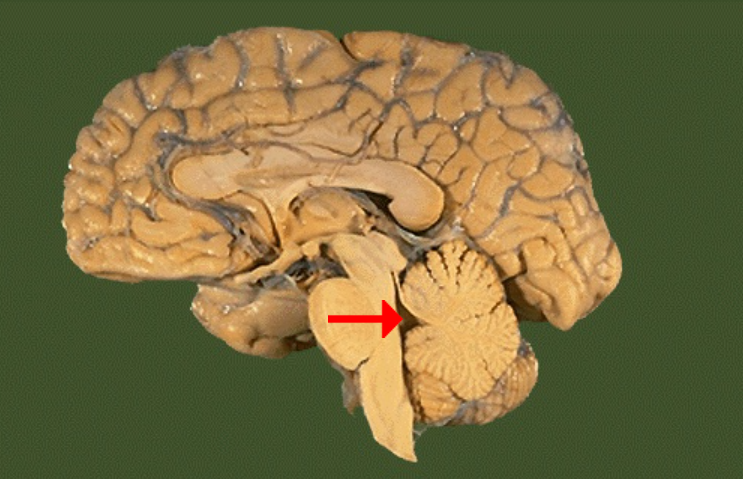

Label this brain part

Tectum (of midbrain)

Label this brain part

Septum pellucidum